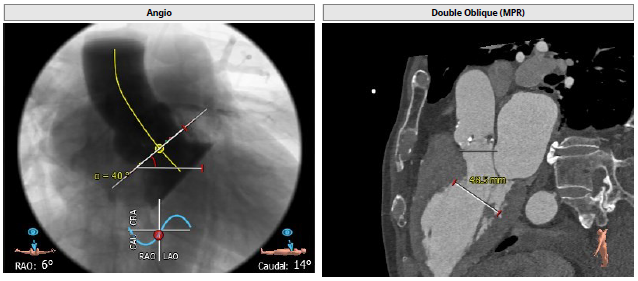

患者为三叶瓣,重度钙化,瓣环29.1 mm,LVOT28.6 mm,预计瓣口开口29.1 mm,STJ 32.3 mm,窦部空间大,左右冠高度分别为16.2 mm和19.8 mm,预计24mm球囊预扩。

主动脉根部造影

交换猪尾测得

主动脉压力87/32mmHg

左心室压力135/8mmHg

压差48mmHg